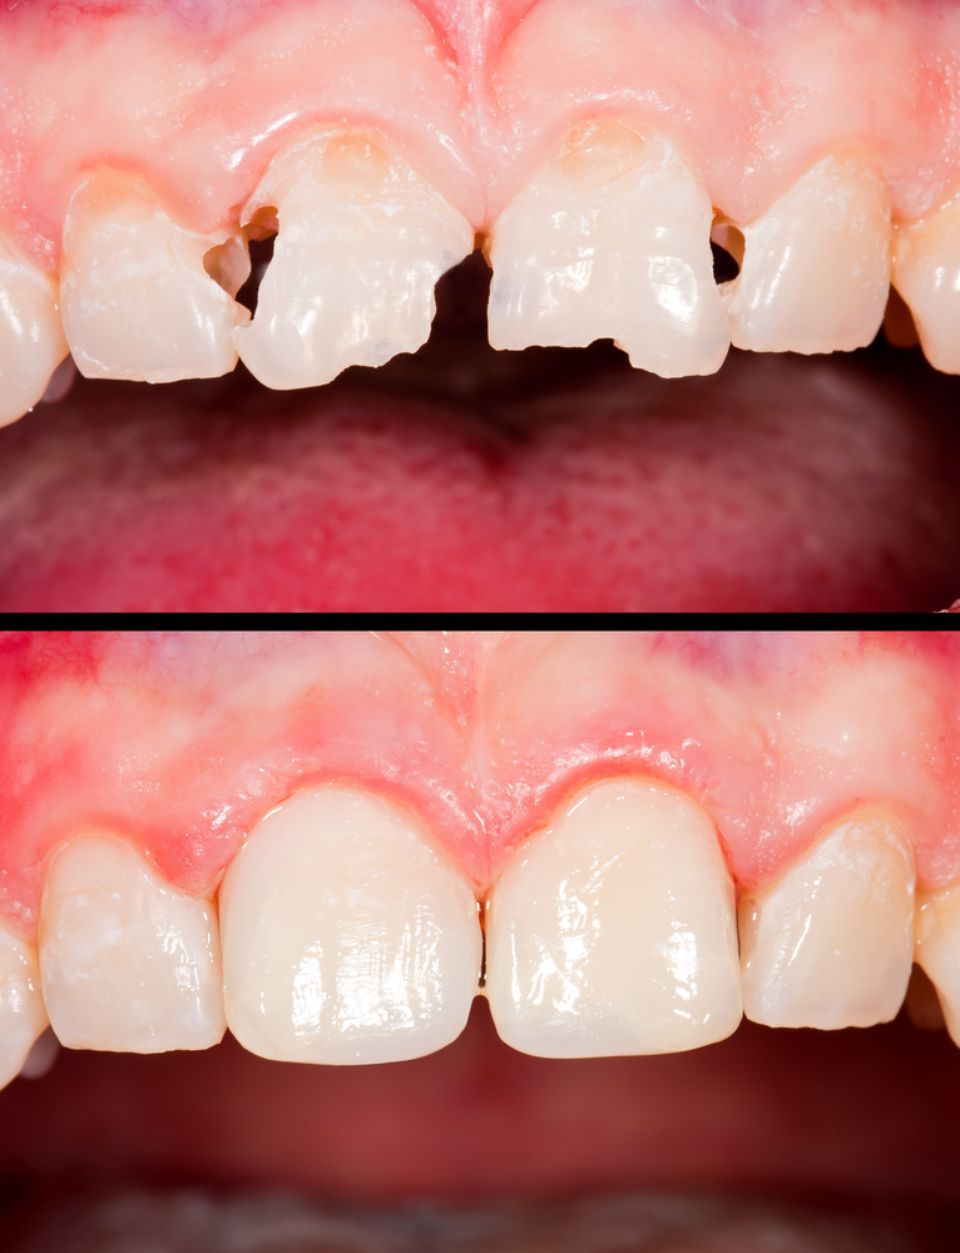

Odontología restauradora/conservadora

Tal y como su nombre indica trata de conservar mediante la reconstrucción de los dientes que se han cariado o se han fracturado, que han sufrido un traumatismo o están erosionados; para preservar su función como diente.

Estética dental

La apariencia de los dientes se puede mejorar. El equipo especialista evaluará cada caso para adoptar la técnica más adecuada: blanqueamiento dental, restauraciones con composite, carillas de cerámica, coronas de metal-cerámica, coronas de circonio, ortodoncia, cirugía estética periodontal ....